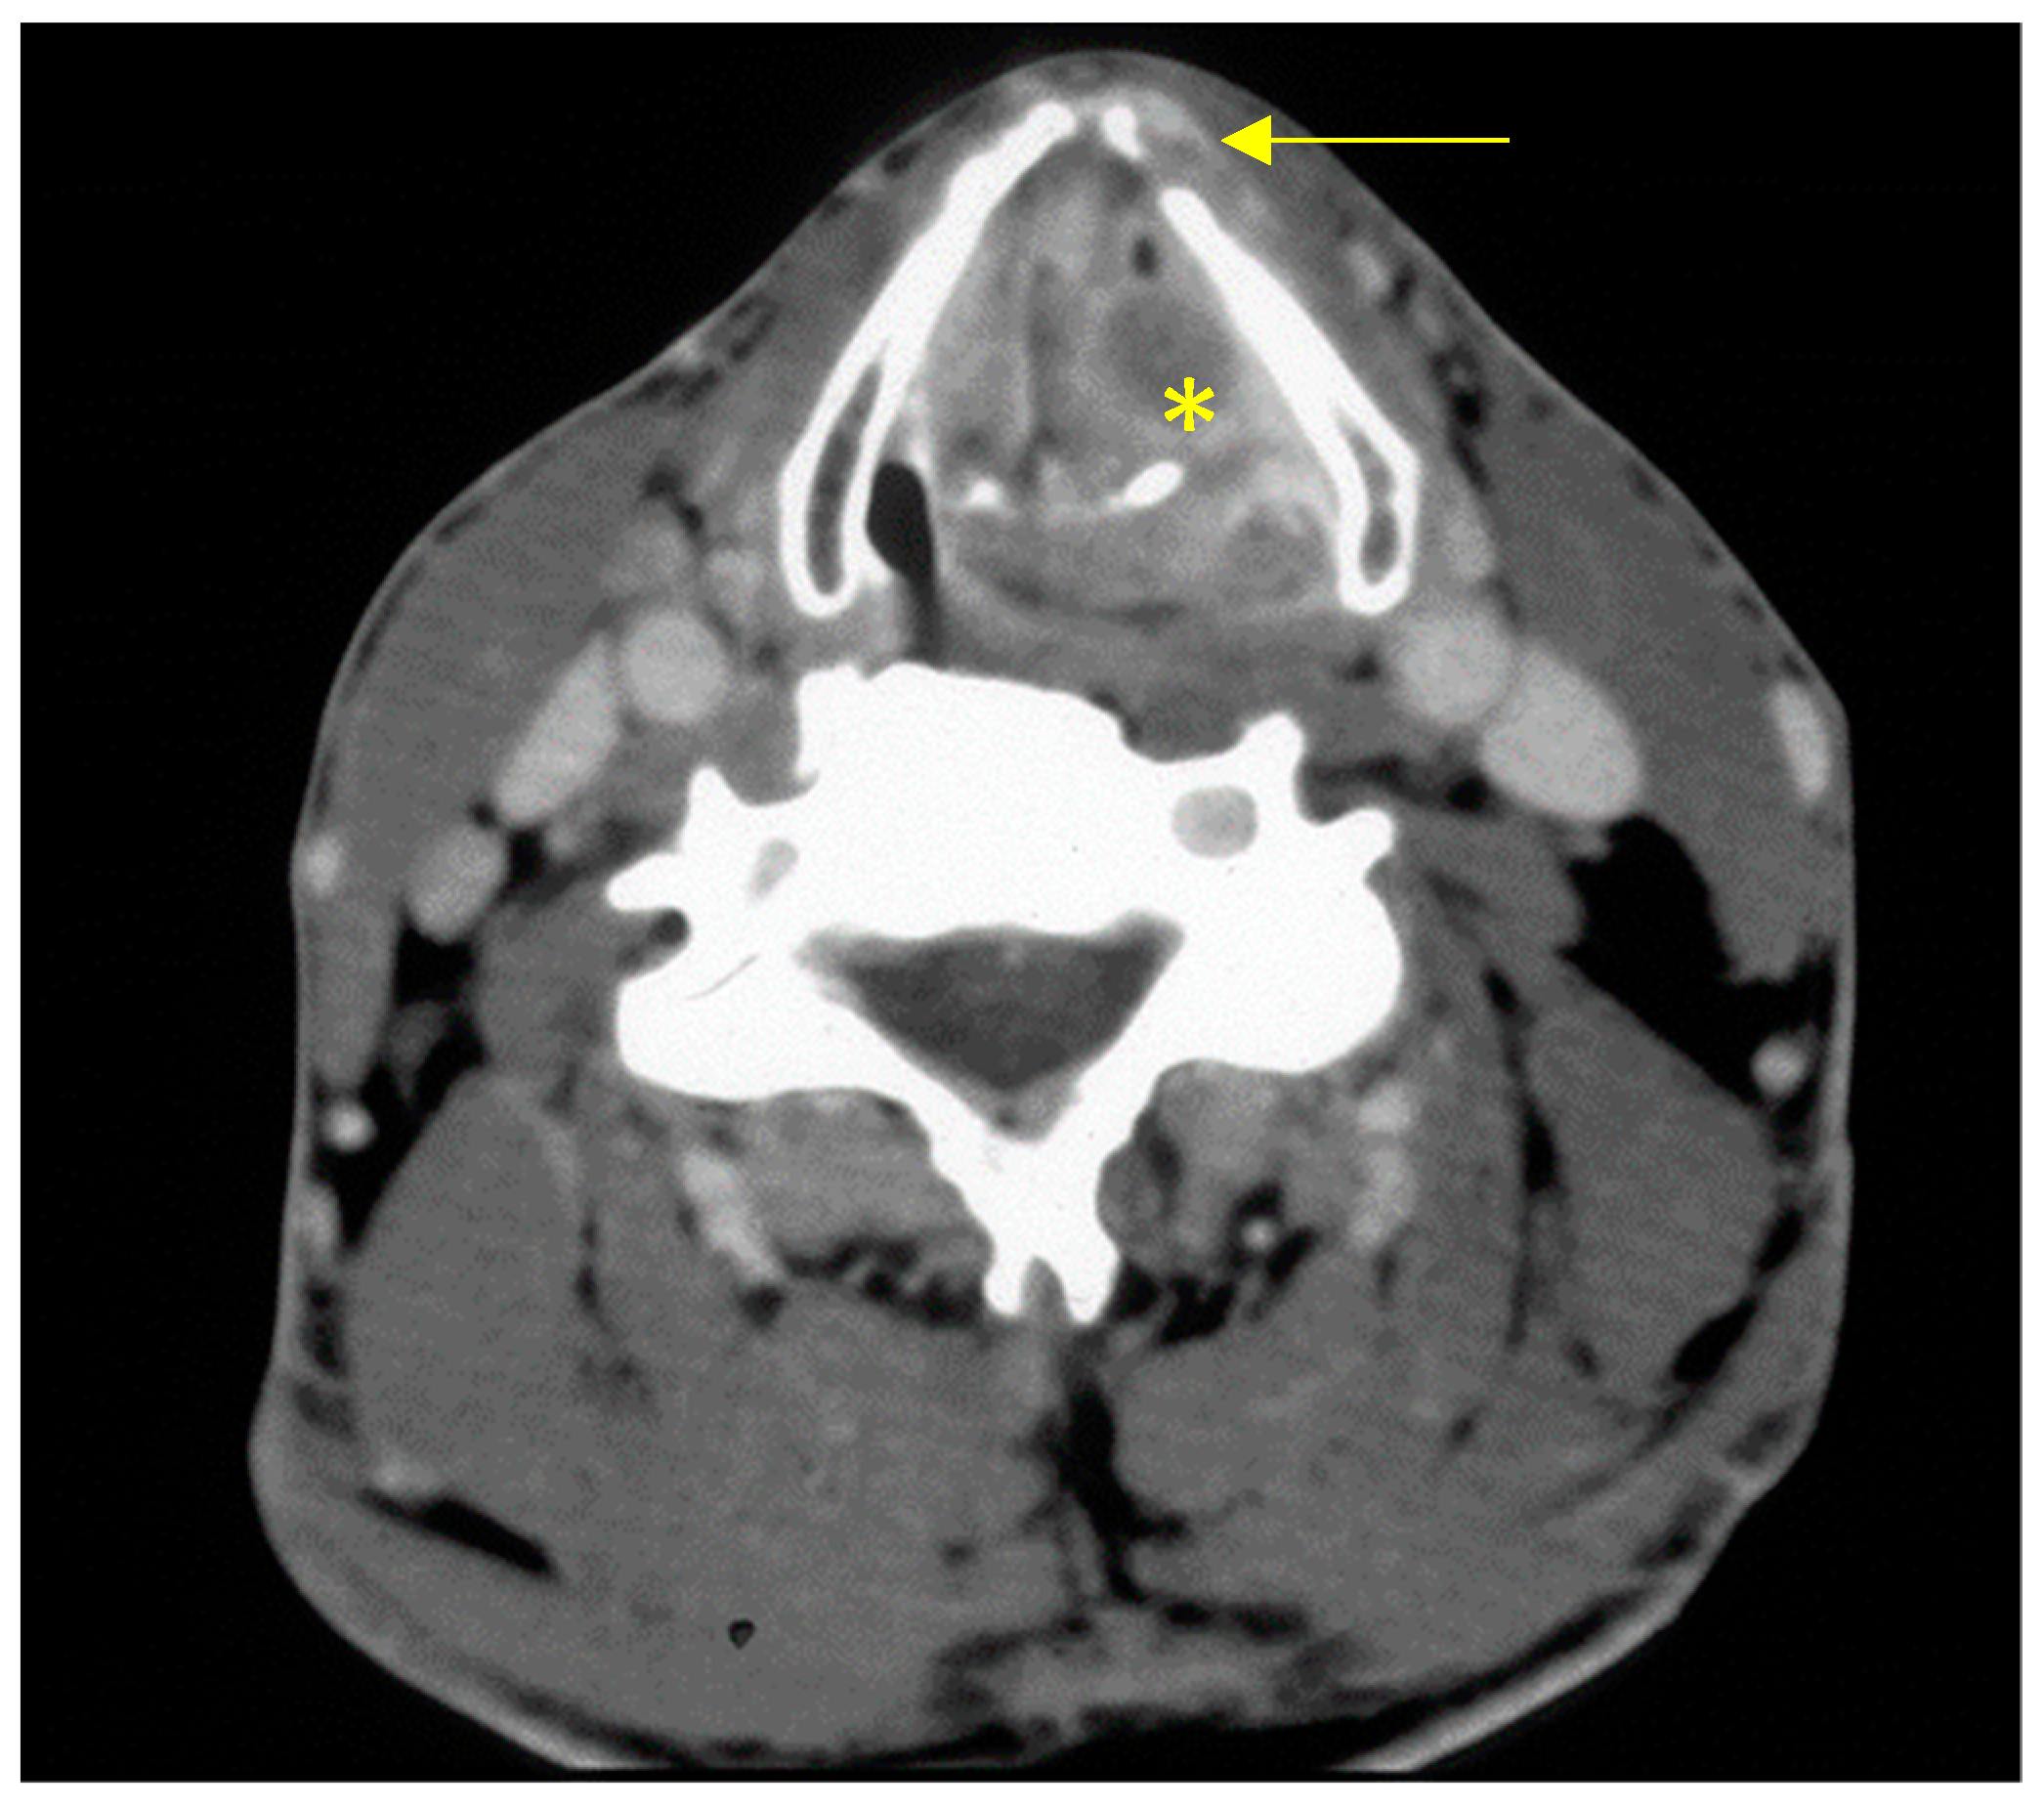

Figure 1.

Image from contrast-enhanced CT of the neck from a patient with transglottic cT4a squamous cell carcinoma of the larynx (yellow asterisk = tumour, arrow = cartilage infiltration).